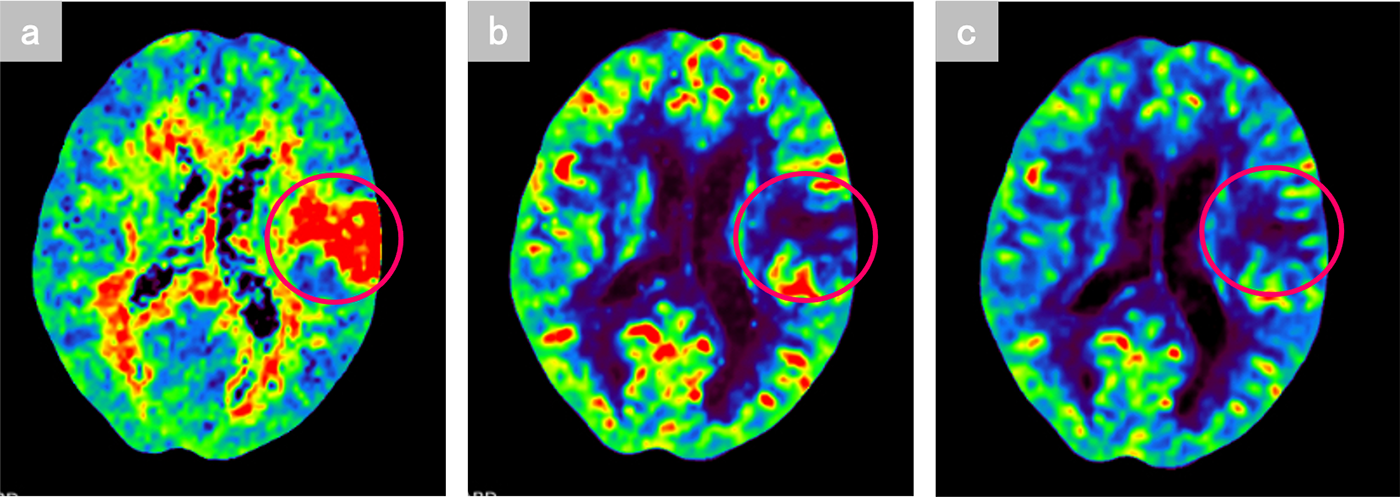

約3時間前発症の脳梗塞疑い。現症は失語。頭部単純CTで異常なし。MRI非対応埋め込み型心臓電気デバイス (CIED) 留置中の患者の為、Perfusion CT+全身アクセスルートの造影CTを施行。

本症例では急性期梗塞の診断目的のPerfusion CTをまず撮影し、5分後に血管内治療用の全身のアクセスルートを撮影した。Perfusion CTでは左前頭葉のブローカ野にMMTの延長、CBF及びCBVの低下を認めた。本症例は発症から3時間程度であったが、CBF、CBVがいずれも低下しており、非可逆性虚血を生じていた。また、左中大脳動脈に粗大な血栓はなく、血管内治療は適応外であった。